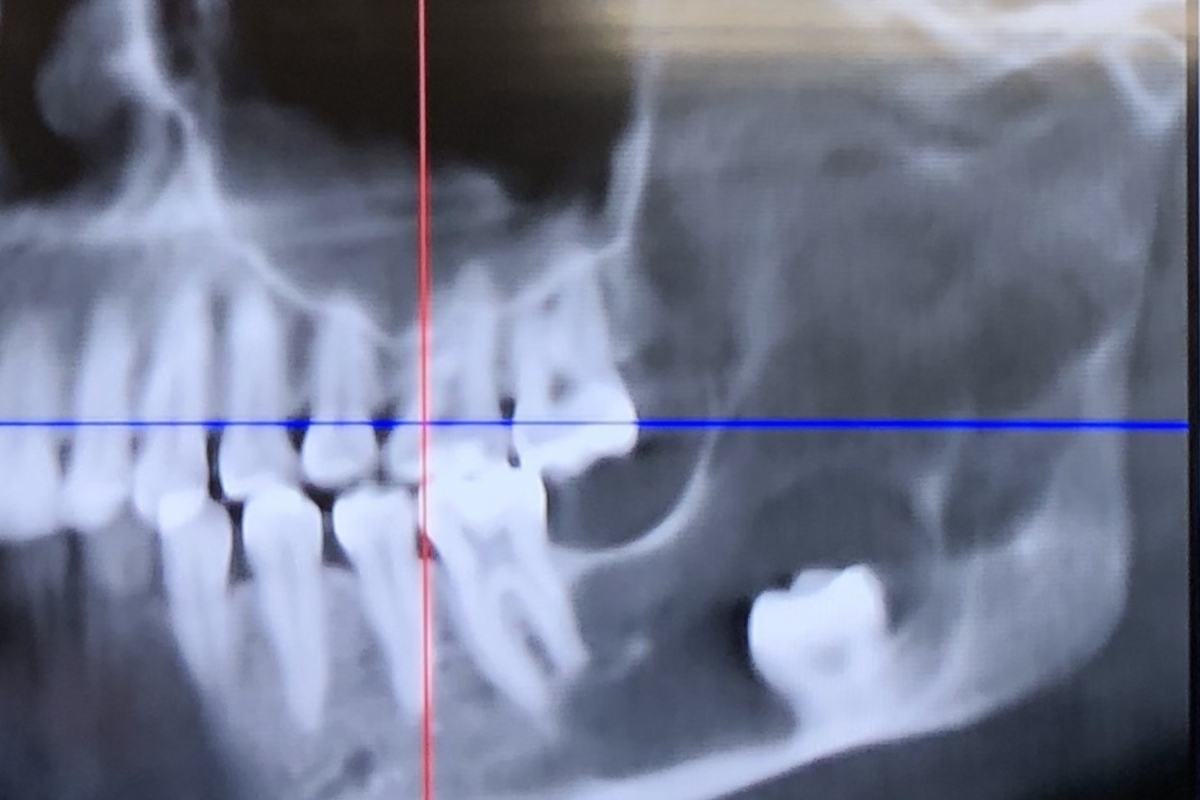

Andrea è stato indirizzato da un chirurgo orale per una TAC per capire meglio perché il dente si era spostato così lontano. I risultati hanno rivelato qualcosa di molto più grave di una semplice estrazione.

La scansione ha mostrato una ciste che cresceva all’interno del lato sinistro della mascella, probabilmente originata dalla sacca che circondava la persona colpita dente del giudizio. La cisti era rimasta inosservata abbastanza a lungo da aver eroso gran parte del suo corpo mascellalasciandolo pericolosamente fragile, fino al cardine.